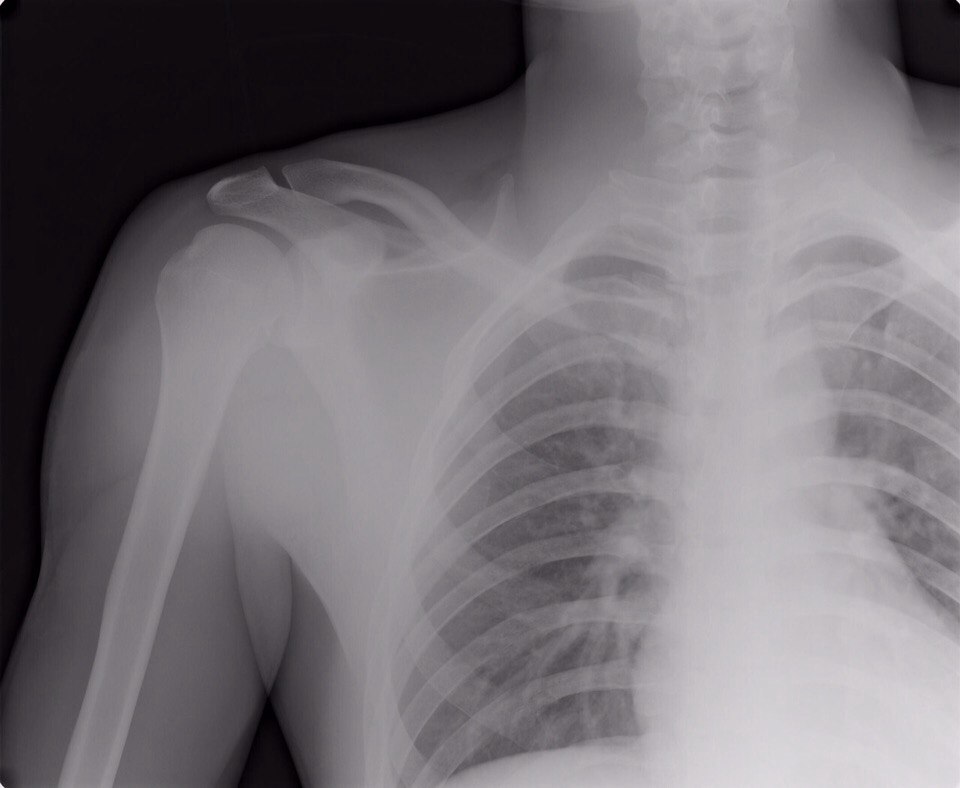

В результате падения в первом заезде на Гран-При Германии, который прошел в минувшие выходные в Тойченталь, у Александра Тонкова серьезная травма плеча и ему предстоит операция уже в эту среду 1 июля. Операция пройдет в Олимпийском центре подготовки спортсменов в Швейцарии.